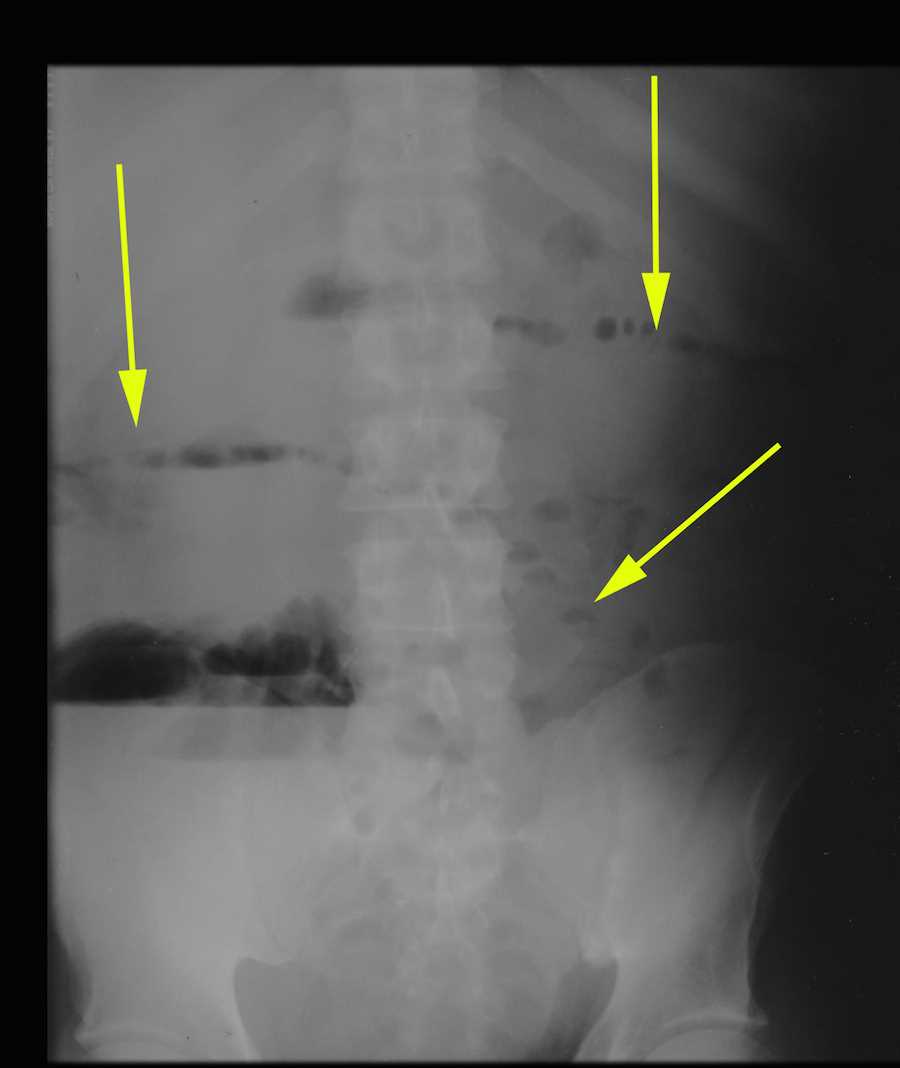

from www.ctisus.com

Recurrent Renal Cell Carcinoma with extensive Metastases Especially to

Recurrent Renal Cell Carcinoma with extensive Metastases Especially to Small Bowel Obstruction Chest Pain The patient described epigastric discomfort and shortness of breath but denied chest pain. An obstruction typically feels like severe cramping pain in your abdomen. Treated by many different types of medical providers, including. Small bowel obstruction (sbo) is a very common problem for patients; Early signs and symptoms of a partial or complete intestinal obstruction include abdominal pain or distention,. Small Bowel Obstruction Chest Pain.